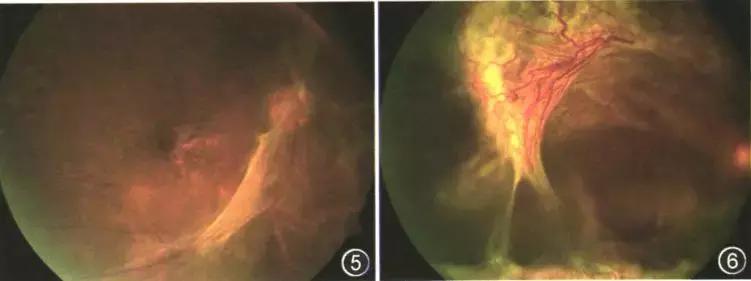

糖尿病视网膜病变是糖尿病导致的视网膜微血管损害所引起的一系列典型病变,是一种影响视力甚至致盲的慢性进行性疾病。在我国,视网膜病变在糖尿病患者人群中的患病率为24.7%-37.5%,其中增生期视网膜病变比例在3.3%~7.4%。

糖尿病视网膜病变的发展是隐匿的,早期患者多无明显症状,当感到视力下降时,病情往往已经发展到严重的阶段。有很多糖尿病患者因严重的视网膜病变导致不可逆转的视力残疾,甚至失明。其实在糖尿病眼病初期,病变可以得到良好的控制。因此,早期诊断和积极干预治疗,阻断或延缓糖网病的发展具有重要的意义。